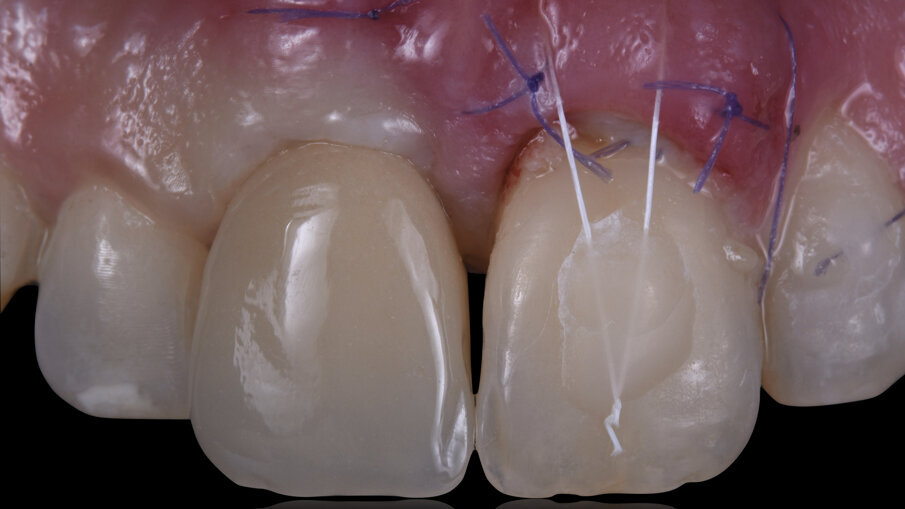

È stata quindi eseguita un’incisione vestibolare intrasulculare del sito senza toccare le papille, facendo scorrere la lama sul piano osseo crestale, e nella porzione più apicale dove era presente la discontinuità della corticale si è spostato la lama mesiale e distale e ancora apicale fino a ritrovare il piano osseo secondo le indicazioni della CBCT; è stato possibile così inserire una membrana in collagene suina Geistlich Bio-Gide (Geistlich Pharma AG, Wolhusen, Switzerland) opportunamente sagomata in modo che avesse un appoggio sui piani ossei (Fig. 4); all’interno dell’alveolo è stato posizionato Geistlich Bio-Oss Collagen (Geistlich Pharma AG, Wolhusen, Switzerland), osso bovino deproteinizzato con un 10% di collagene suino addizionale, materiale osteoconduttivo che oltre a essere mantenitore di spazio e scaffold per la rigenerazione ossea, funge anche da sostegno per il tessuto molle soprastante (Fig. 5). Si è quindi proceduto dopo anestesia palatale a un prelievo tramite bisturi circolare di un punch epitelio connettivale di forma tondeggiante e misure simili all’alveolo dell’1.1 da sigillare; dopo la disepitelizzazione dei margini dell’alveolo si è proceduto alla sutura del punch al di sopra del sostituto osseo con suture Vicril 6-0 (Johnson & Johnson Medical Spa, Pomezia RM, Italia) con punti staccati alle quattro estremità e sutura a materassaio esterno incrociato compressiva (Fig. 6). In questa fase la paziente è stata riabilitata con un maryland bridge in composito cementato adesivamente.

La paziente è stata dimessa con terapia farmacologica di supporto e a due settimane si è proceduto alla rimozione delle suture riassorbibili e i controlli clinici sono stati eseguiti poi a 1 mese, 3 mesi e 5 mesi. Al termine della fase di maturazione dei tessuti (5 mesi) (Fig. 7) si è evidenziato come da un punto di vista clinico siano stati mantenuti i volumi sul piano verticale (addirittura più coronali di circa 2 mm rispetto al centrale contro-laterale 2.1) e sul piano trasversale vestibolo palatale, e inoltre il nuovo esame CBCT evidenziava la ricostruzione della parete ossea vestibolare (Fig. 8).